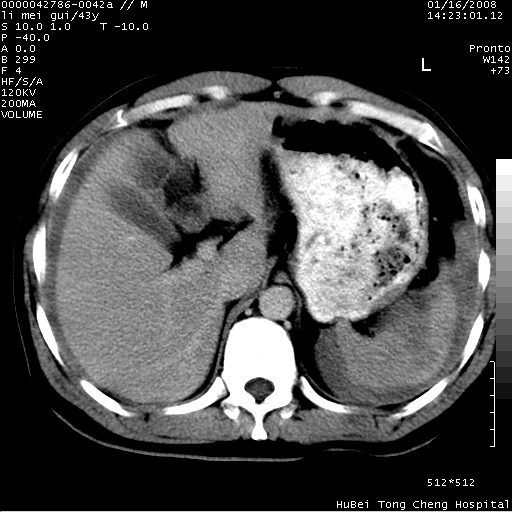

| 患者,男,43岁。突发腹痛2小时,面色苍白,难以平卧。自述近期无明确外伤史,为摩托车驾驶员。 腹部b超检查:脾脏中上极回声异常,肿瘤待排。 临床诊断:腹痛原因待查。 上中腹部ct轴位平扫+增强扫描(层厚10mm,螺距1.0,重建间隔10mm),图像如下: ![]() ![]() ![]() ![]() ![]() ![]() ![]() ![]() ![]() ![]() ![]() ![]() ![]() ![]() ![]() ![]() ![]() ![]() ![]() ![]() ![]() ![]() ![]() ![]() ![]() ![]() ![]() ![]() ![]() ![]() ![]() ![]() ![]() ![]() ![]() zrs发言:支持脾破裂 wwp发言:支持脾破裂并腹水。 xulianj发言:脾脏肿瘤破裂可能性大 zsl6918发言:不像肿瘤出血,考虑还是与外伤后引起的慢性出血有关 zzyy发言:平扫见肝周及脾周积液,脾内密度不均。脾内肿瘤较少见。还是外伤性脾破裂。 沈丘东方医院发言:脾门区一个不均匀强化病灶与其周液体相连多考虑脾占位破裂出血 yixianman001011发言:脾破裂并腹水是可以肯定的,具体原因多以肿瘤性破裂出血,脾脏淋巴瘤可能性大. 结果: 术后,经详细询问患者,其仔细回忆:一月前骑摩托时左侧腰部与别人有“轻微”触碰,因责任在自已,当时又无明显不适,未引起注意。 临床术后诊断:脾破裂并失血性休克(1.外伤性迟发性脾破裂。2.脾脏肿瘤破裂?) 术后标本病检:脾破裂并出血,未见明显肿瘤成份。 原贴地址:http://www.radinet.com.cn/forum_view.asp?forum_id=4&view_id=34070 |